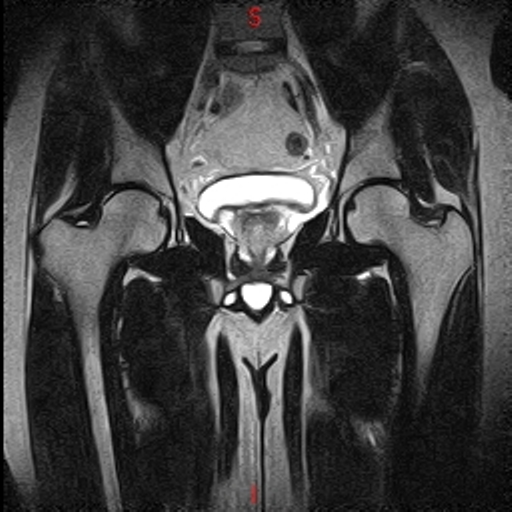

• Resonancia NORMAL CADERAS T2 CORONAL

• Resonancia NORMAL CADERAS T1 CORONAL